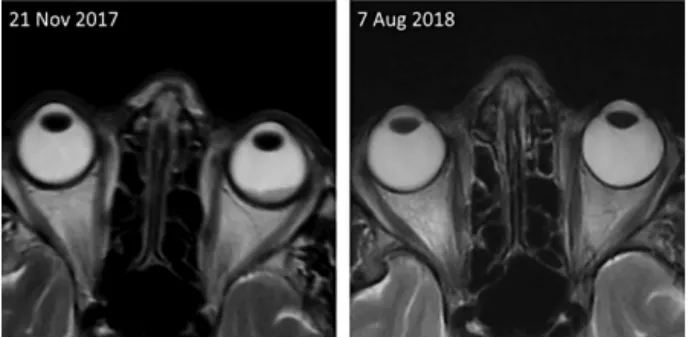

数天后,患者视力下降,转诊眼科。检查发现一个非色素性脉络膜视网膜肿瘤,很可能与乳腺癌转移相关,导致浆液性脱离。MRI显示至少有5个脑转移瘤和1个眶内转移瘤,视网膜增厚与眼科报告相符,还有1个颅骨转移瘤。

2个月后随访的第一阶段显示治疗有效,肺和肝转移瘤的大小均缩小了50%以上。头部MRI显示脑转移瘤稳定,视网膜转移灶缩小50%以上。患者恢复正常视力后无症状,无呼吸困难。因此,阿那曲唑和ribociclib的治疗仍在继续。

一阶段8周后的第二阶段,包括脑转移在内的所有转移灶体积均缩小(表1);眶内转移灶完全缓解(图1)。病人自述生活质量非常好。

图1.头部MRI显示治疗开始时眶内转移导致黑色素(左),8.5个月后完全缓解(右)。